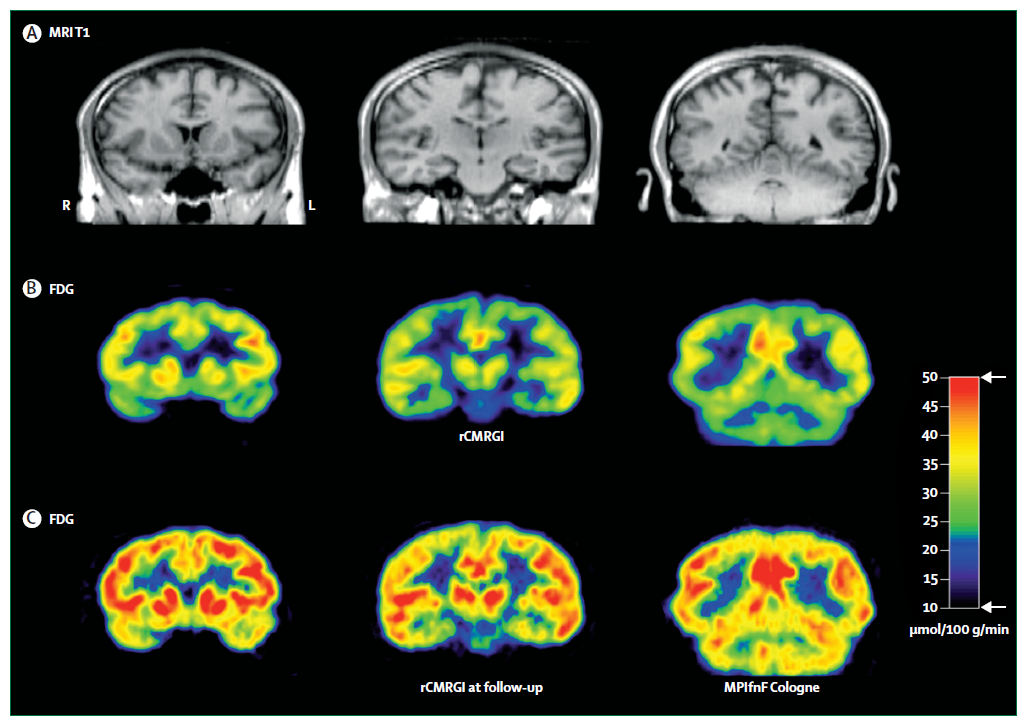

- Neuroimagen funcional: Con el fin de observar si hay disminución en la activación de las regiones temporales y frontales derechas o alteración en las conexiones cortico-límbicas.